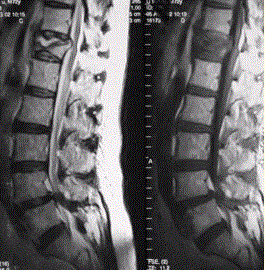

问题 患者男,70岁,因肝癌入院,准备行肝移植手术。住院期间因腰扭伤而腰痛,故行腰椎MRI检查(如下图)。 关于压缩性骨折椎体的特点,描述正确的是

选项 A.椎体后缘平直 B.椎体后缘弧形后凸 C.椎体后缘局部信号正常 D.椎体内可见长T1长T2液体信号影 E.椎体后上角后凸,压迫硬膜囊 F.椎体前后缘呈弧形突出,且前后径明显加长

答案 ACDE

解析 ACDE